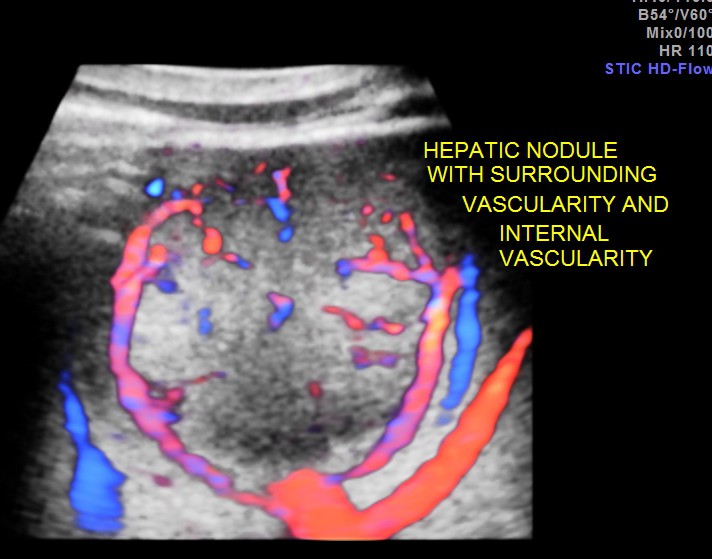

An echogenic nodule with vascularity is seen.

3 d reconstruction shows the solid nature and vascularity around and within the nodule.

The appearance of this nodule was suggestive of a metastatic nodule with the increased vascularity around and within.